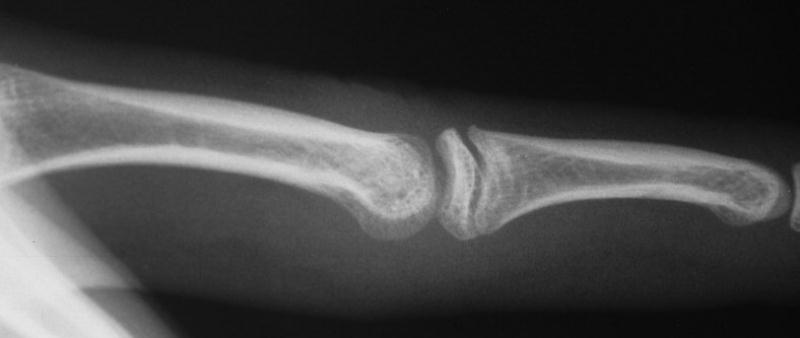

Case 3. 21 year old woman with pain developing in a congenitally angulated thumb.

Radiographs show a juxtaarticular ossification with  subchondral cyst formation of the bone interface with the lateral phalangeal head and lateral angulation of the proximal phalanx articular surface.